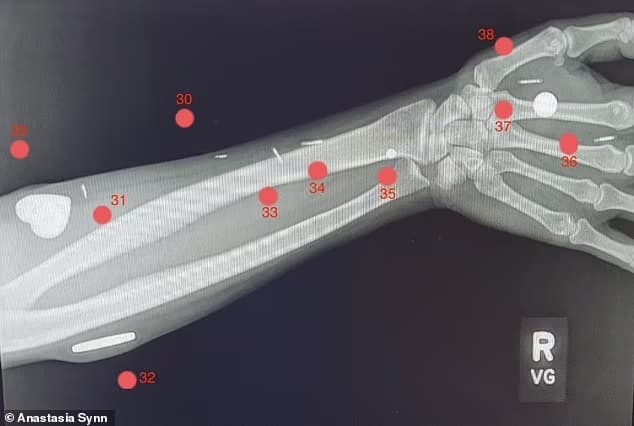

Σε σχετικά σύντομο χρονικό διάστημα – μόλις έξι χρόνια – η Anastasia έφτασε από το να μην έχει εμφυτεύματα στο νούμερο ρεκόρ των 52.

Οι λειτουργίες των μικροσκοπικών αντικειμένων περιλαμβάνουν το άνοιγμα κλειδαριών με το κούνημα του χεριού, την εύρεση μαγνητικών αντικειμένων, ακόμη και την ενεργοποίηση συντομεύσεων σε ένα smartphone. «Ένα πράγμα που μου αρέσει στα εμφυτεύματά μου είναι ότι δεν μπορείς πραγματικά να δεις κανένα από αυτά – δεν ξέρεις πού βρίσκονται» ανέφερε.

• 30. Τσιπ RFID που όταν σαρώνεται δίνει έναν αριθμό που “σαν χαμένο κατοικίδιο” θα εμφανίσει μια σελίδα για τον εκλιπόντα σύζυγο

• 31. Μικροτσίπ με δυνατότητα σάρωσης NFC δίπλα στις στάχτες του εκλιπόντος συζύγου που εμφανίζει το μνημείο του.

• 32. Τεράστιος κυκλικός μαγνήτης στο δεξί χέρι

• 33. Μικροτσίπ με δυνατότητα σάρωσης NFC που ενεργοποιεί μια κλήση στο τηλέφωνο του εκλιπόντος συζύγου.

• 34. Μικροτσίπ με δυνατότητα σάρωσης NFC, το οποίο όταν σαρώνεται εμφανίζει το βίντεο από το μνημόσυνο του εκλιπόντος συζύγου.

• 35. Αισθητικός μαγνήτης στον δεξιό καρπό που της επιτρέπει να αισθάνεται ηλεκτρομαγνητικά πεδία

• 36. Τσιπ RFID που μπορεί να ανοίξει ένα

με κλειδαριές

• 37. Βαθιά τοποθετημένος κυλινδρικός μαγνήτης στην παλάμη του δεξιού χεριού, που χρησιμοποιείται σε μαγικές παραστάσεις

• 38. Μικροτσίπ NFC στον ιστό του δεξιού χεριού. Προς το παρόν προγραμματισμένο να ανοίγει το αγαπημένο της μείγμα μουσικής ska